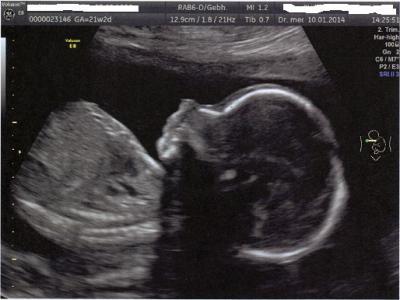

Hallo Mädels, also es ist alles so wie es sein sollte, er ist jetzt ca. 25 cm groß und 420 g schwer. Alle Werte gut, auch Durchblutung, Plazentalage ist auch schön weit oben. Geschlecht war wieder eindeutig, der Papa hat sogar ein Beweisfoto bekommen :). Lustig ist, dass er an der Mundpartie total viel Ähnlichkeit mit meiner Tochter hat. Haben mal ein Bild von ihr aus der 21. SSW daneben gelegt. An anderen Stellen ist dagegen garkeine Ähnlichkeit da *hüstel*. Eindeutig, wie gesagt. Namen sind wir noch am Überlegen, aber der Erstname steht fest: Benaja. Lg an euch alle und ein schönes Wochenende!

Schön dass alles in Ordnung ist. Ach und das Bild ist ja süss...!!!! Lg